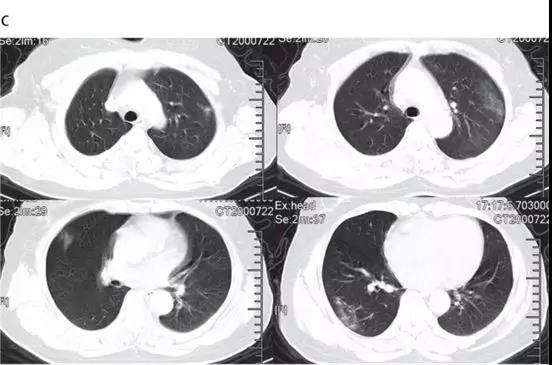

非ICU患者的代表性胸部CT检查表现为双侧毛玻璃样混浊和亚段实变(见下图)。

随后的胸部CT显示双侧毛玻璃样混浊,而实变消除(见下图)。